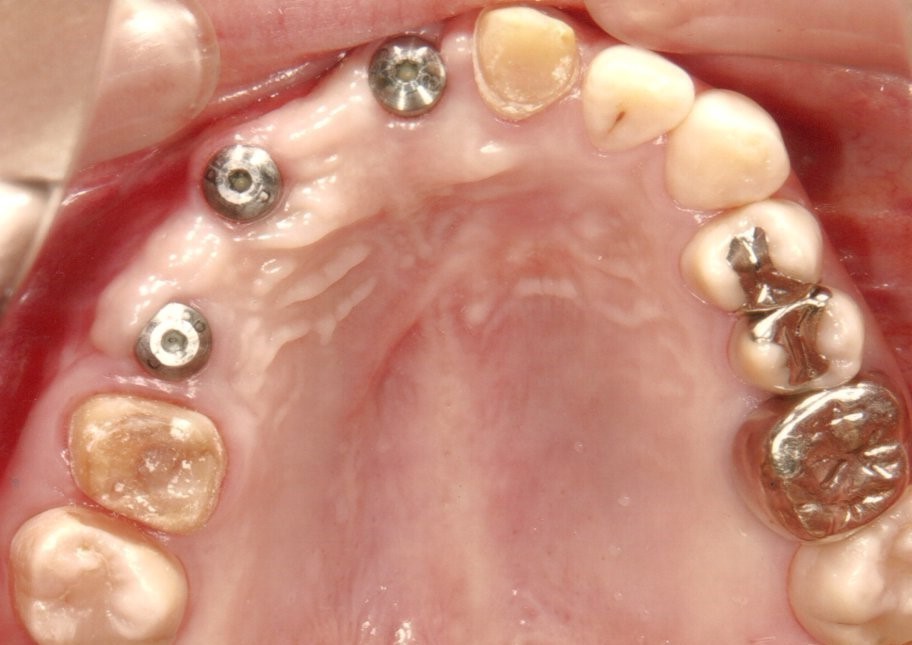

奥歯インプラント(スクリュー固定)

(伊東市 女性)

治療の流れ

むし歯で歯を失ってしまいました。

インプラントを埋入し、最終的な被せ物を装着しました。(ネジ穴をふさぐ前)

ネジ穴をふさぐとこの様な状態になります。

インプラント手術:250,000円

静脈内鎮静法:0円

既製アバットメント:90,000円

メタルボンド:130,000円

総額:470,000円+税